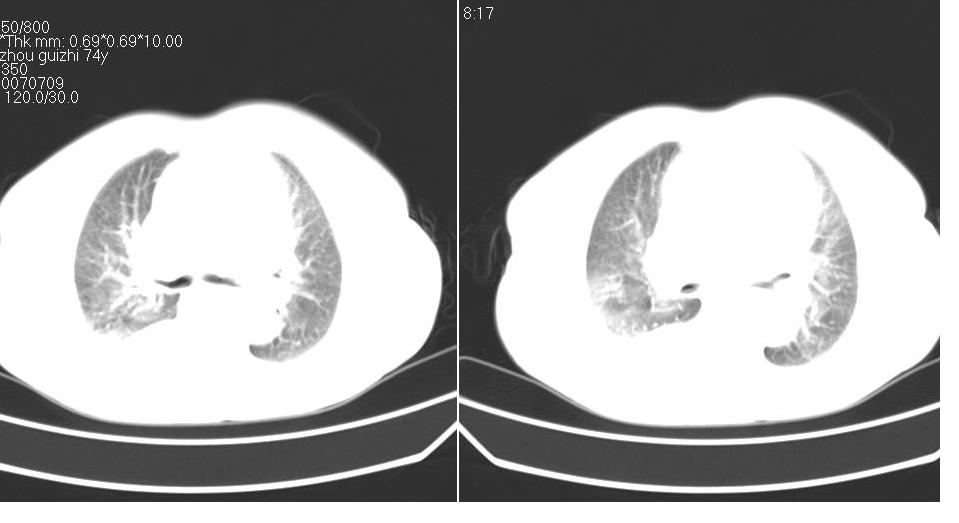

以下是引用liaizhi在2007-7-11 15:41:00的发言:[br]两肺纹理增粗,肺门影增大,气管支气管通畅。升主动脉壁及冠状动脉壁钙化。左房左室稍扩大。心包积液,胸腔积液。考虑冠心病并心功能不全,肺水肿,胸腔积液。

以下是引用zhangzhongshou在2007-7-11 13:16:00的发言:[br]1、冠状动脉钙化[br]2、心包积液[br]3、右侧胸腔积液[br]大家都考虑心衰,冠状动脉钙化、肺纹理增强,胸腔积液、心包积液,表面上是支持,但是为什么右侧有较多积液,左侧没有呢? 如果用结核性胸膜炎,并结核性心包炎也可解释,请楼主进一步提供临床资料。

以下是引用yanghaochen88在2007-7-11 9:00:00的发言:[br]冠心病、心包积液、胸水,心衰结合临床。